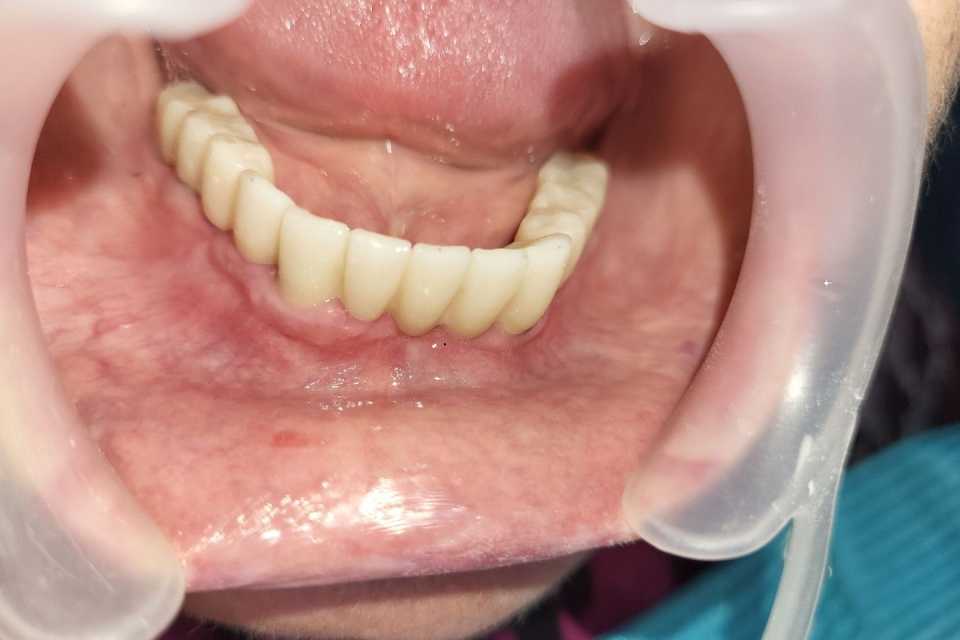

Planul de tratament a inclus extracția dinților parodontotici la nivelul mandibulei și inserarea a 5 implanturi dentare Mega-Gen AnyRidge cu conexiune multiunit, urmată de protezarea acestora cu o lucrare fixă, înșurubabilă, din ceramică pe suport de zirconiu.